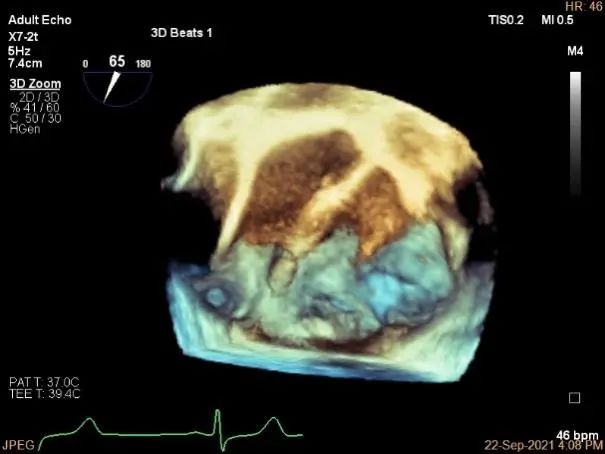

3D:P1区脱垂并腱索断裂,Width:11.4mm

3D-color:重度MR,4级

MVA:7.8cm²,平均跨瓣压差:1mmHg